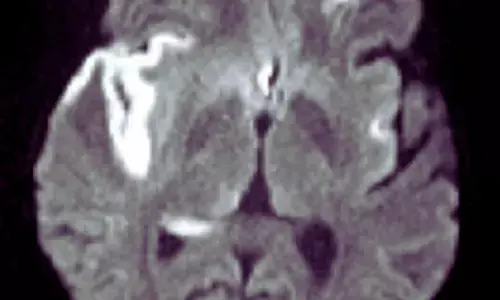

Dexamethasone Adds No Verbal Memory Benefit in Herpes Simplex Virus Encephalitis: The Lancet

UK: In a phase III trial involving patients with herpes simplex virus encephalitis, adding dexamethasone to acyclovir did not improve verbal memory...